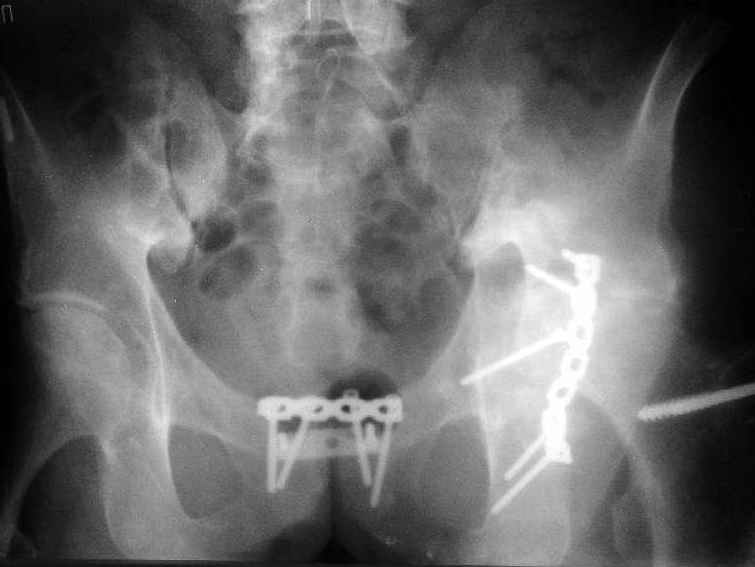

Пациент 53 лет травма 25.11.02. в салоне автомашины, получил множественные переломы ребер с ушибом легких и гемопневмотораксом, ротационно нестабильное повреждение таза: перелом боковых масс крестца, разрыв лонного сочленения, оскольчатый поперечный юкстатектальный перелом левой вертлужной впадины с центральным вывихом бедра и сегментарным переломом головки, перелом крыла правой подвздошной кости. Открытый многооскольчатый перелом костей правого предплечья, перелом правого бедра в нижней трети, перелом надколенника слева, перелом лодыжек левой голени с переломом заднего края левой большеберцовой кости подвывмхом стопы.Бедро срослось на вытяжении, лодыжки в гипсе, предплечье в аппарате. Под наше наблюдение попал 25.03.03. Выполнен чрескостный остеосинтез таза, с постепенной коррекцией положения отломков, затем 28.04.03 реконструкция вертлужной впадины для эндопротеза, синтез лонного сочленения. В настоящее время ходит с костылями, беспокоят боли в левом тазобедренном суставе, прогрессирует деформация головки. То есть в ближайших планах - эндопротезирование этого сустава. Однако смущает ряд моментов: В частности, на стороне предполагаемого эндопротезирования (левой) имеется разрыв собственной связки ниже надколенника, который подпаян к бедру (видно на фото сидя), то есть активного разгибания голени нет. А на правой стороне имеется штыкообразная деформация бедра, нет полного разгибания коленного сустава, хотя конечность опороспособна; ортопедическое укорочение 3 см.Вопросы: Что делать с левым надколенником и 4-главой мышцей? Восстанавливать ли ось и длину правого бедра? Если не трогать правое бедро, то на сколько компенсировать укорочение при эндопротезировании?